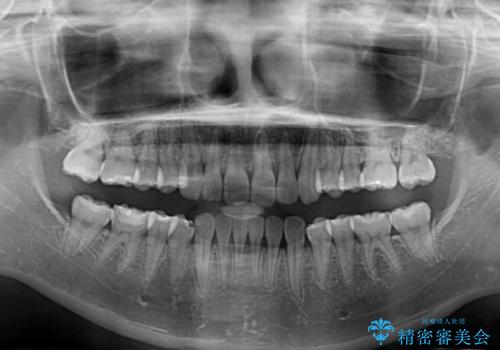

- 口元の深い咬み合わせ(ディープバイト)を気にして来院された患者様です。

インビザラインによる上下歯列の遠心移動(後方移動)により、口元のデコボコとディープバイトを改善することとしました。

下顎左右の犬歯とその後ろにある第一小臼歯、計4歯がシミュレーション通りに動かずディープバイトがなかなか改善されませんでした。

マウスピースの再製作を何度か行いましたがうまくいかないため、部分的にワイヤー矯正を併用することを提案しました。しかし、最も気になっていた前歯のデコボコはきれいに改善されたため、これ以上治療を希望されず、治療を終了することとしました。(今後気になった際には再開する予定です)